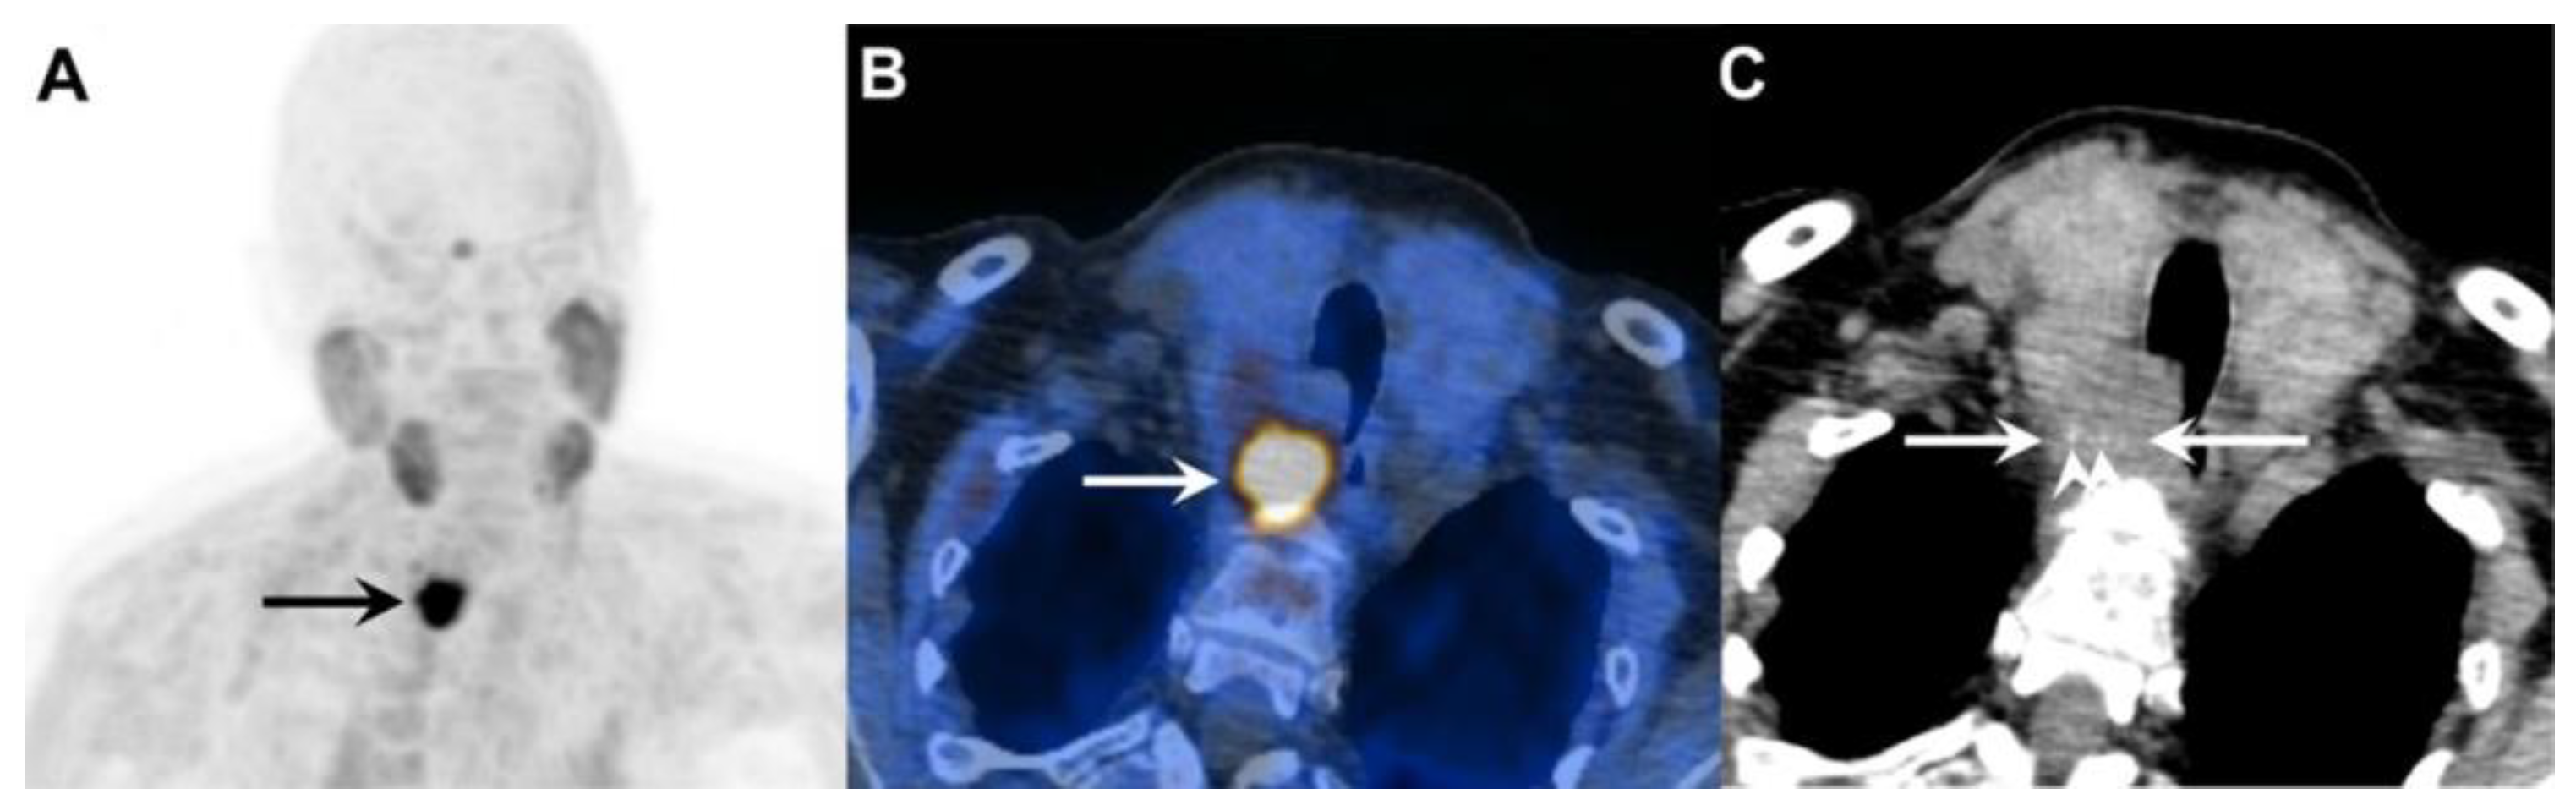

[18F]fluorocholine is a PET tracer that undergoes phosphorylation by choline kinase, an enzyme central to phospholipid synthesis in cell membranes. Hyperfunctioning parathyroid tissue—particularly adenomas and carcinomas—shows upregulated choline metabolism, leading to marked tracer accumulation. Compared to traditional scintigraphy, [18F]fluorocholine PET/CT(MR) imaging provides several key advantages: markedly improved spatial resolution (4–5 mm vs. 10–15 mm), shorter acquisition time (approximately 30 min vs. 2–3 h), higher contrast-to-background ratio, and lower radiation exposure, particularly when performed with PET/MR imaging [42]. Figure 4. demonstrates an example of PC detected on [18F]fluorocholine PET/CT.

Figure 4. A 73-year-old woman with primary hyperparathyroidism due to parathyroid carcinoma. Legend: (A) Coronal [18F]fluorocholine PET maximum intensity projection (MIP) image demonstrates an intensely tracer-avid lesion in the neck (black arrow, SUVmax 18.9). (B) Axial fused [18F]fluorocholine PET/CT image shows the tumor (white arrow) located deep to the right lobe of the enlarged thyroid gland. (C) On the corresponding unenhanced CT image, there is loss of the fat plane between the tumor (white arrows) and surrounding structures, with intralesional stippled calcifications visible (white arrowheads).

A notable limitation, as with all radiotracers, is that [18F]fluorocholine PET cannot reliably distinguish benign adenomas from localized PC, as both demonstrate increased choline metabolism with overlapping standardized uptake values (SUV). However, the presence of a large cervical mass with intralesional calcifications, in conjunction with pathologic lymph nodes or lesions suspicious for distant metastases, is highly suggestive of PC rather than benign disease. Hence, when malignancy is clinically suspected, whole-body [18F]fluorocholine PET/CT(MR) imaging is recommended for comprehensive staging.